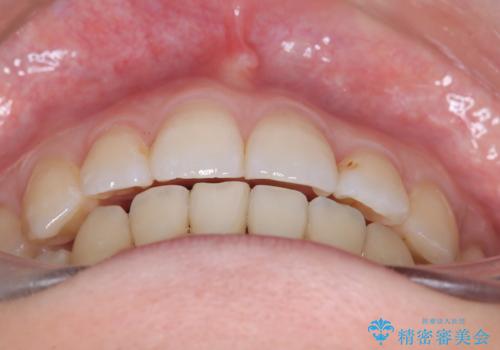

【ワイヤー矯正】口元を下げたい、下の歯の凹凸を無くしたい

- 主訴:口元を下げて前突感を無くしたい、下の歯の凹凸も無くしたい

右側第二小臼歯、左側第一小臼歯、下顎両側第一大臼歯を抜歯しワイヤ-矯正を行いました。

骨格的顎の変位を認めたため、顔貌に対しピッタリ上下の歯の正中を合わせることは難しいと説明し、上下左右計4本小臼歯を抜歯しワイヤー矯正治療を行いました。